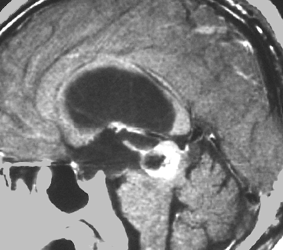

放射線化学療法後の画像です。腫瘍境界は不明瞭(左)で,腫瘍内出血(中央)して,左の視床に浸潤しています。かなりリスクは高いのですが,これを開頭手術で全摘出しました(右),この時点で完全寛解 CR です。この後にさらに化学療法と幹細胞移植(PBSCT,大量化学療法)が加えられました。